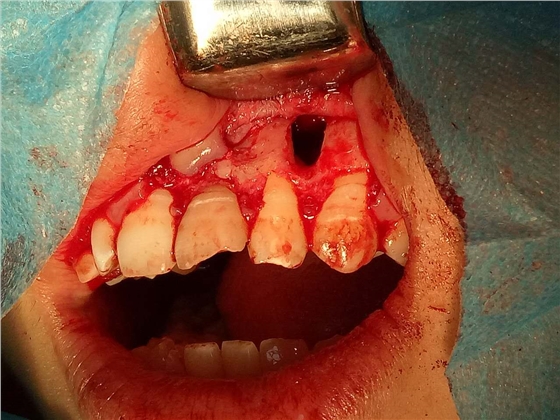

死髓牙2度,沒保留價值了,外傷造成的外吸收,即使到充也容易出問題。和患者溝通,要求做種植,用了兩個骨膠原,側切、尖牙沒事,側切做了一次根充